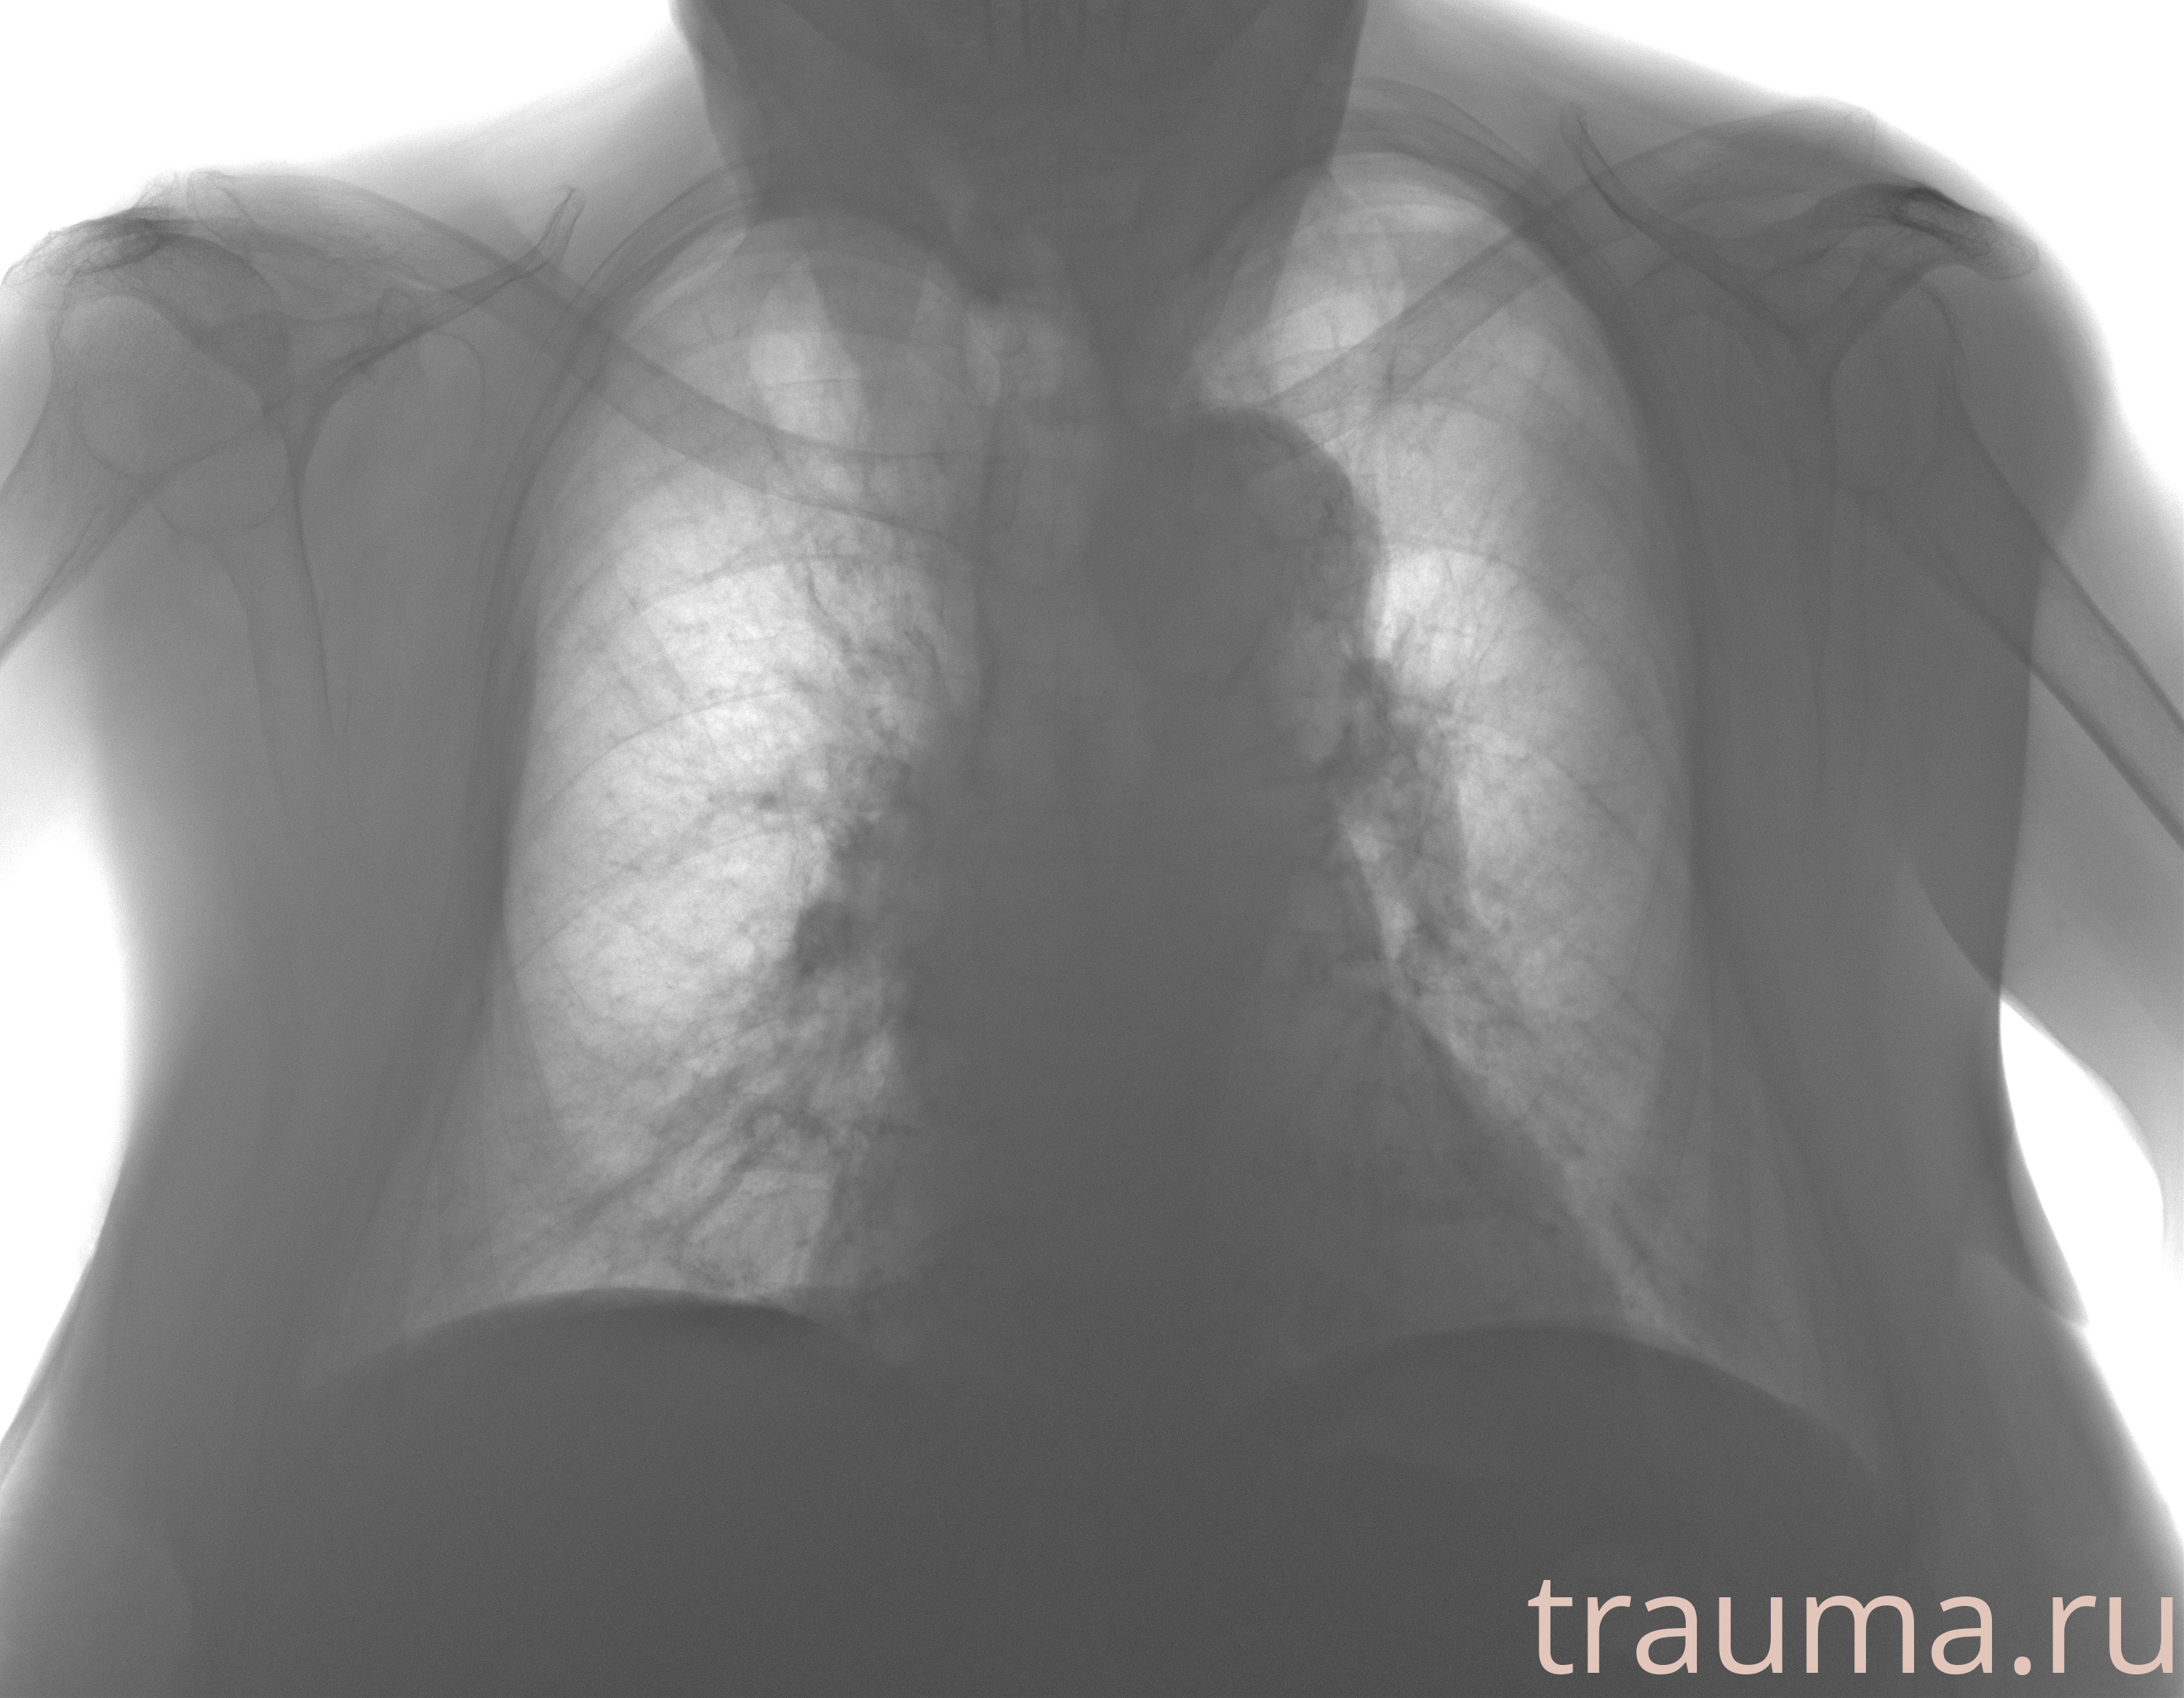

Рентген на дому: по вашему адресу приезжает врач-рентгенолог, травматолог-ортопед с мобильным рентгеновским аппаратом, проводит диагностику травмы или заболевания, делает необходимые рентгенограммы, дает рекомендации по дальнейшему лечению. Получить качественные снимки в домашних условиях возможно благодаря уникальной методике, разработанной МосРентген Центром для института  Склифосовского

при переломе шейки бедра и пневмонии от компании МосРентген Центр - партнера Института имени Склифосовского